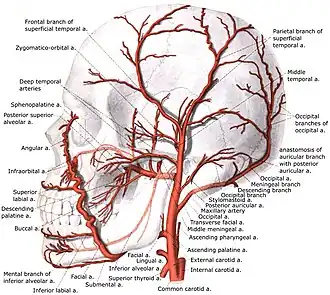

Branches

As the artery travels upwards, it gives the following branches:

- In the carotid triangle:[3]

- Superior thyroid artery, arising from its anterior aspect

- Ascending pharyngeal artery - arising from medial, or deep, aspect

- Lingual artery - arising from its anterior aspect

- Facial artery - arise from its anterior aspect

- Occipital artery - arising from its posterior aspect

- Posterior auricular artery - arising from posterior aspect

The external carotid artery terminates as two branches:

The superior thyroid artery anastomoses with inferior thyroid artery, where the latter arises from thyrocervical trunk of the subclavian artery.[2]

Terminal branch of facial artery anastomose with ophthalmic artery of internal carotid artery.[2]

Posterior auricular artery anastomose with occipital artery, another branch of external carotid artery.[2]

One of the branches of superficial temporal artery anastomose with lacrimal and palpebral branches of ophthalmic artery.[2]

Branches of external carotid artery

Branches of external carotid artery